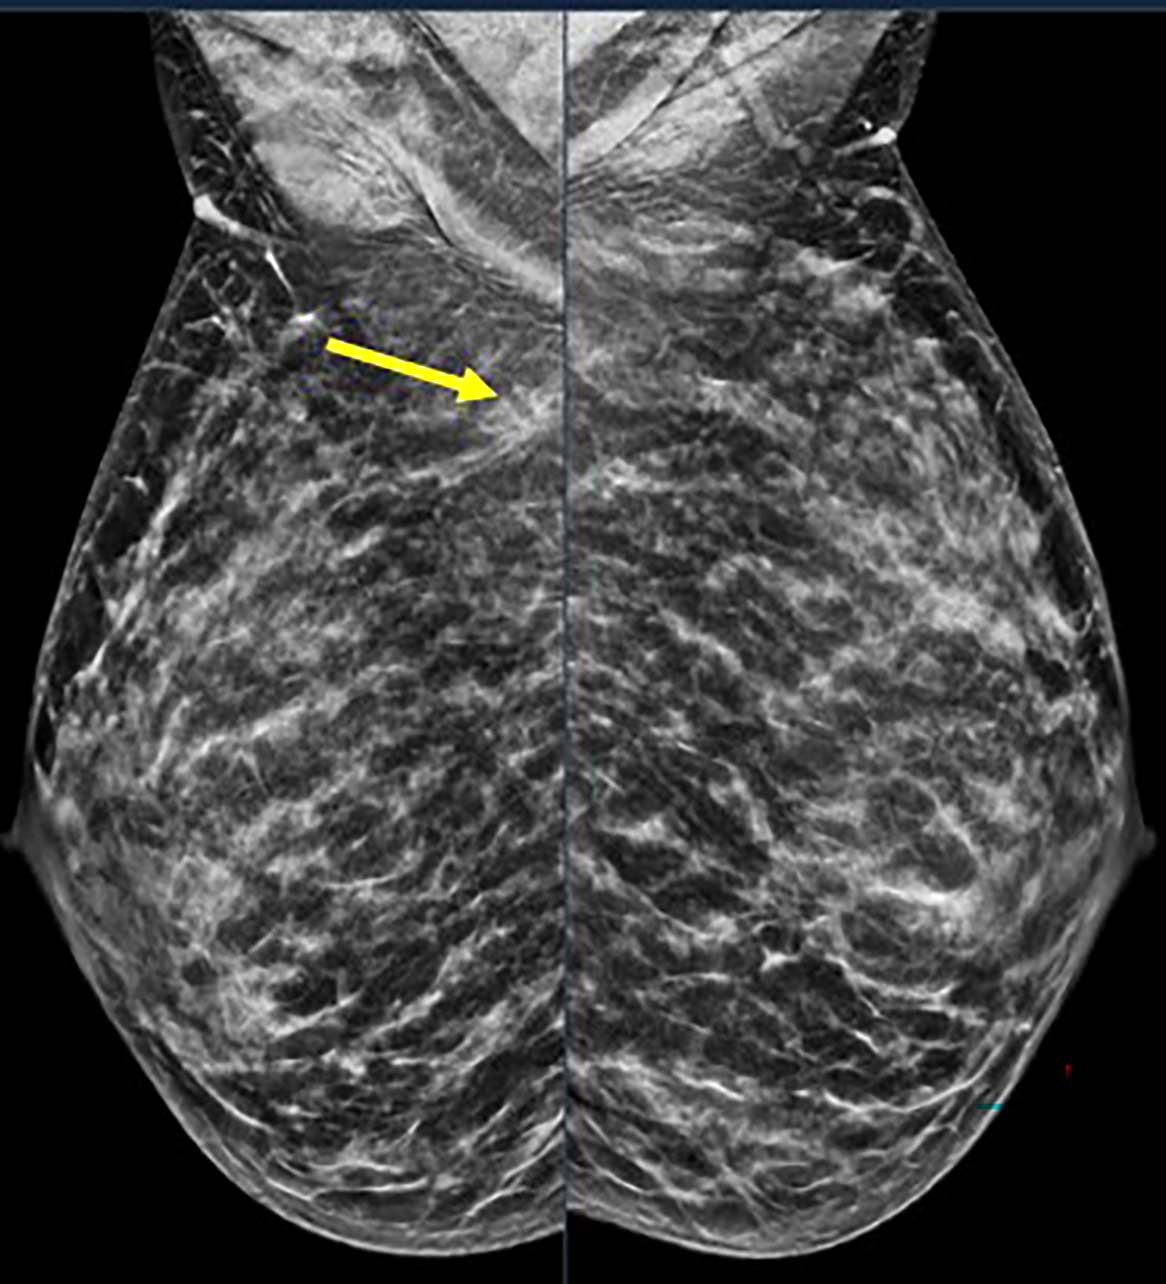

بالنسبة للنساء اللاتي يعتبرن متوسطات الخطورة، توصي فرقة العمل المعنية بالخدمات الوقائية بالولايات المتحدة بإجراء تصوير الثدي بالأشعة كل عامين بدءًا من سن 40 عامًا وتستمر حتى سن 74 عامًا. وتنصح جمعية السرطان الأمريكية بإجراء تصوير الثدي بالأشعة السينية سنويًا بدءًا من سن 45 عامًا، مع خيار البدء بين سن 40 إلى 44 عامًا. قد تُنصح النساء اللاتي لديهن مخاطر أعلى بسبب عوامل محددة بالخضوع لكل من التصوير بالرنين المغناطيسي للثدي والتصوير الشعاعي للثدي كل عام بدءًا من سن 30 عامًا تقريبًا، ولكن لا توجد حاليًا إرشادات فحص رسمية للنساء الأصغر من ذلك.

شرع الدكتور ديستونيس ومدير أبحاث EWBC أندريا إل أرينو، بكالوريوس العلوم، في تحديد حالات سرطان الثدي التي تم تشخيصها من عام 2014 حتى عام 2024 عبر سبعة مرافق للمرضى الخارجيين تغطي مساحة 200 ميل في غرب نيويورك. تمت مراجعة جميع أنواع السرطان لدى المرضى الذين تتراوح أعمارهم بين 18 إلى 49 عامًا باستخدام تقارير التصوير السريري.

وقال الدكتور ديستونيس: “لقد جمعنا على وجه التحديد تفاصيل حول كيفية اكتشاف السرطان (الفحص أو التشخيص)، ونوع السرطان، وخصائص الورم الأخرى”. “لقد استبعدنا الحالات التي لم تكن سرطان الثدي الأولي. وقمنا بتحليل الاتجاهات مع مرور الوقت حسب المجموعات الفرعية العمرية، وطريقة الكشف، وبيولوجيا الورم. وقد ساعدنا هذا على تحديد كيفية ظهور سرطان الثدي في هذه المجموعة من المرضى، ومدى تكرار حدوثه، وأنواع الأورام الموجودة.”